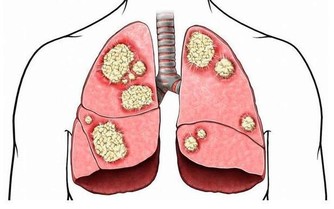

麻疹(Measles)是一種由麻疹病毒引起的急性傳染病,其傳染性極高,是目前全球公共衛生的重要議題之一。麻疹主要通過空氣中的飛沫傳播,也可以透過與受感染者的密切接觸傳播。其典型症狀包括高燒、咳嗽、流鼻涕、結膜炎(紅眼)以及紅色斑點狀皮疹,常被誤以為是普通感冒或過敏反應。然而,麻疹可能引發嚴重的併發症,包括肺炎、腦炎,甚至死亡。